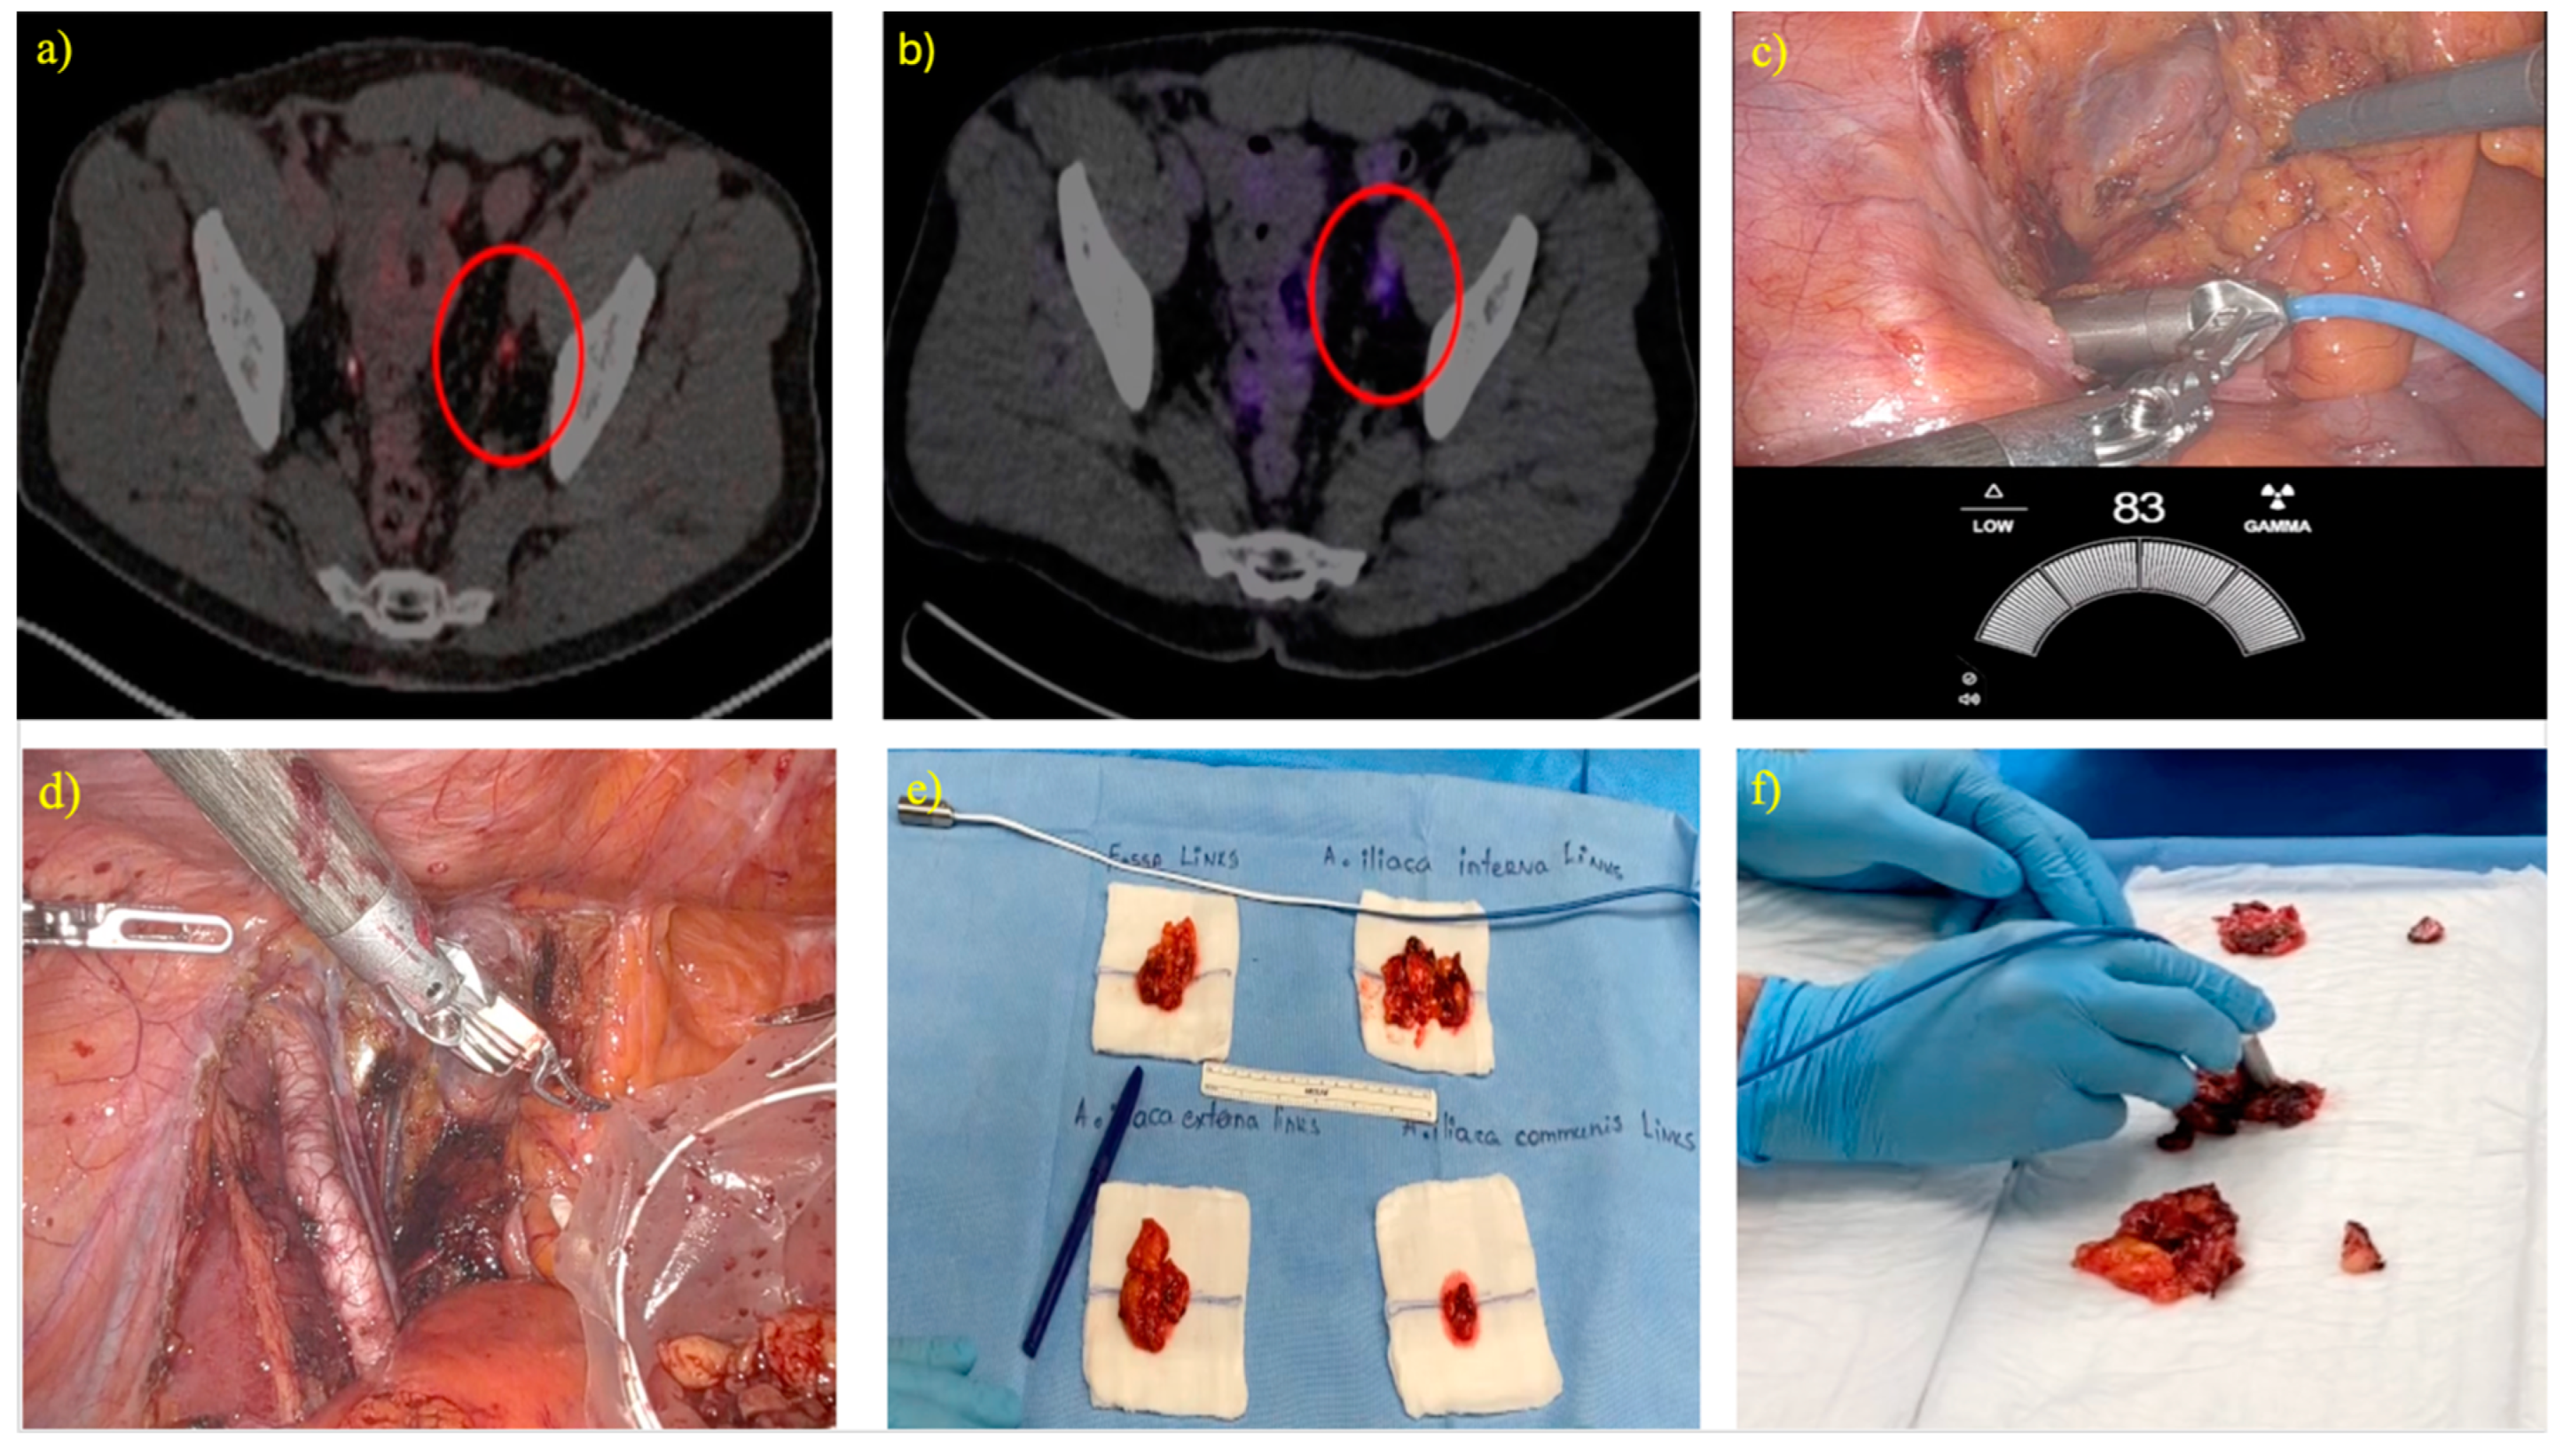

Robot-Assisted PSMA-Radioguided Salvage Surgery for Oligorecurrent Prostate Cancer Using the Novel SENSEI® Drop-in Gamma Probe: Correlation of Intraoperative Measurements to Preoperative Imaging and Final Histology

3.3. Correlation of Intraoperative Radioactivity Measurements and Preoperative PSMA PET/CT